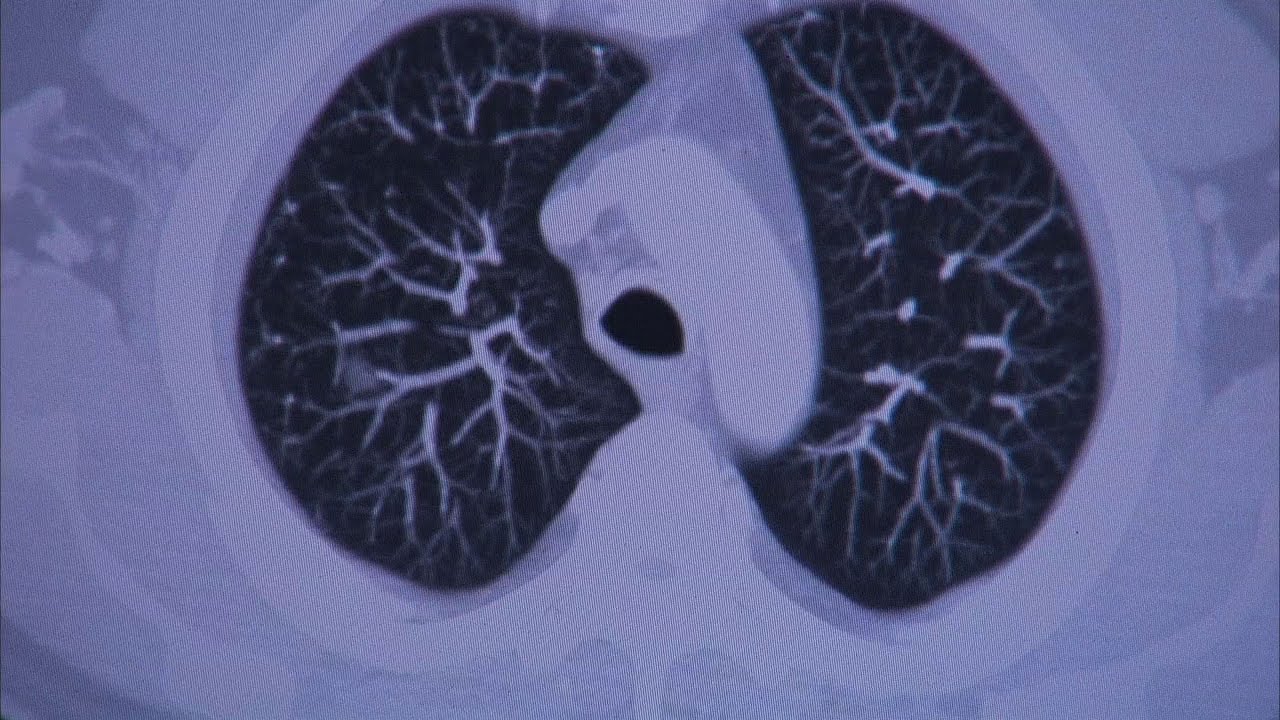

The symptoms of colorectal cancer can be very vague or nonspecific says mayo clinic gastroenterologist dr. Rest of sept, all of october i fell a lot. Ground glass is an appearance on a ct of a cluster of lung cells that have changed. Shanda blackmon outlines some of those causes and how you can cut your risk. Lung cancer and chronic obstructive pulmonary diseases: This aggressive form of lung cancer most commonly occurs in smokers. According to mayo clinic q&a, radon is created by the natural breakdown of uranium in soil, rock and water. When signs of the disease start to appear, they can include: The inset shows three swollen lymph nodes below the lower jaw. Bronchoscopy is a procedure that lets doctors look at your lungs and air passages. Bronchoscopy is most commonly performed using a. One of the most common places to find swollen lymph nodes is in the neck. The good news is colorectal cancer is treatable, especially if diagnosed early.

In this project, researchers in the epidemiology and genetics of lung cancer research program at mayo clinic are clarifying possible associations between chronic obstructive pulmonary disease (copd) and lung cancer.